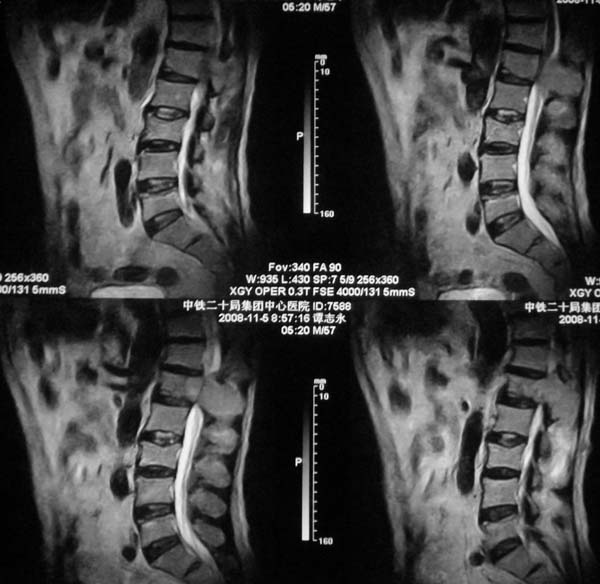

病史特点:

1.中年男性

2.腰疼,双下肢麻木1月。

3.ct 可右肾上腺占位,腰1椎体及附件可见骨质破坏及软组织肿块。

4.mri:腰1椎体及附件t1wi低信号,t2wi高信号。

考虑右侧肾上腺癌骨转移.或右肾上腺及骨均为转移瘤。